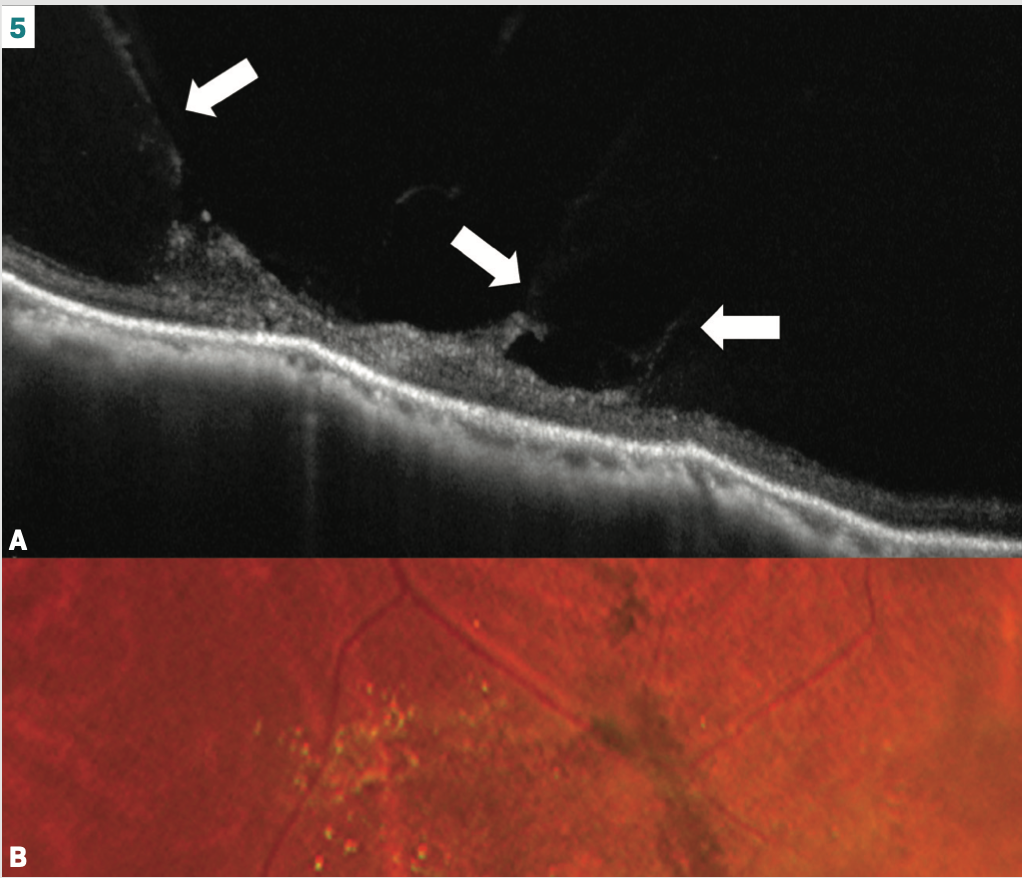

Seeing is believing: lattice and vitreoretinal interaction

Lattice degeneration presents in about 10% of patients, with a 50% chance of bilaterality.6,10 Retinal thinning is a common finding.10 Exaggerated vitreoretinal attachments and overlying vitreous liquefaction tend to occur (Figure 3B, asterisk). The vitreous traction can be striking with P-OCT (Figure 5A). It is no wonder, then, that lattice poses a risk, albeit small, for retinal detachment.